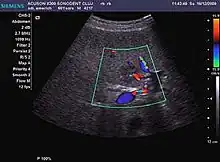

It is a tumor developed secondary to a circulatory abnormality with abundant arterial vessels having a characteristic location in the center of the tumor, within a fibrotic scar. A radial vessels network develops from this level with peripheral orientation. The tumor's circulatory bed is rich in microcirculatory and portal venous elements. The incidence is higher in younger women and tumor development is accelerated by oral contraceptives intake. 2D ultrasound appearance is a fairly well-defined mass, with variable sizes, usually single, solid consistency with inhomogeneous structure. Rarely the central scar can be distinguished. Spectral Doppler examination detects central arterial vessels and CFM exploration reveals their radial position. CEUS examination shows central tumor filling of the circulatory bed during arterial phase and completely enhancement during portal venous phase. During this phase the center of the lesion becomes hypoechoic, enhancing the tumor scar. During the late phase the tumor remains isoechoic to the liver, which strengthens the diagnosis of benign lesion.